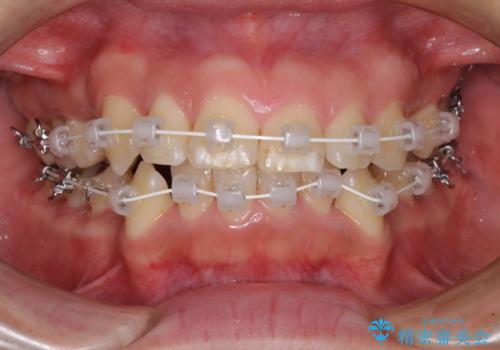

- 矯正装置

- 審美装置

- 1年8ヶ月

当初予定は2年半程度と伝えていましたが、2年にも満たない期間で治療を終えることができました。